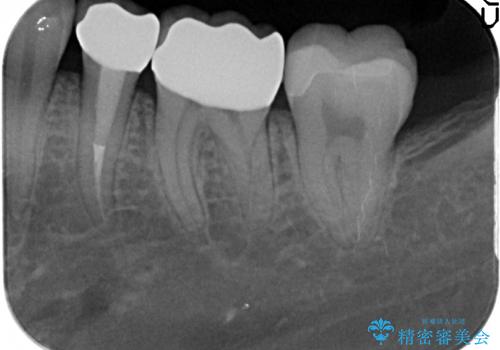

- 左下奥歯の銀歯が気になると来院された方の症例です。

左下7はセラミックインレーによる修復を行い、左下5、6はオールセラミッククラウンによる補綴を行いました。

- オールセラミッククラウン…¥100,000×2、仮歯…¥10,000×2、ファイバーコア…¥20,000、セラミックインレー…¥70,000費用は治療当時の料金となります